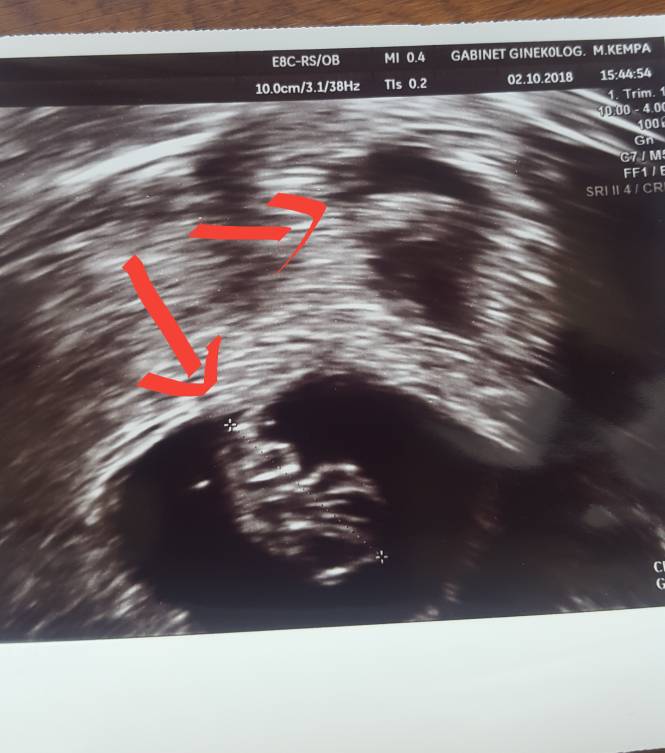

Może ja też się pochwalę zdjeciem fakt że mało jeszcze widać ale ciężko dwoje uchwycić na jednym [emoji4]hehe nastepne usg 30.10 ehhh.. nie wiem czy się doczekam[emoji38][emoji38] Zobacz załącznik 905598